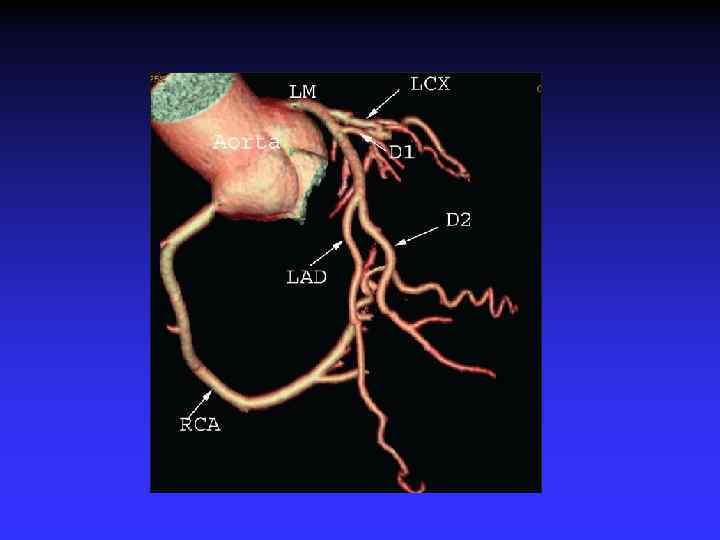

Coronary CTA